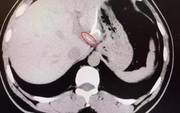

• Nam sinh trung học sốt 5 ngày rồi tử vong, bác sĩ cảnh báo: Bệnh phổ biến nhưng không thể xem nhẹ

Nam sinh trung học sốt 5 ngày rồi tử vong, bác sĩ cảnh báo: Bệnh phổ biến nhưng không thể xem nhẹ

Nam sinh xuất hiện sốt và nhiều biểu hiện khó chịu nhưng trì hoãn điều trị suốt 5 ngày. Khi được gia đình đưa vào khoa cấp cứu, em đã trong tình trạng kiệt sức toàn thân. Kết quả kiểm tra khiến bác sĩ không khỏi bàng hoàng.